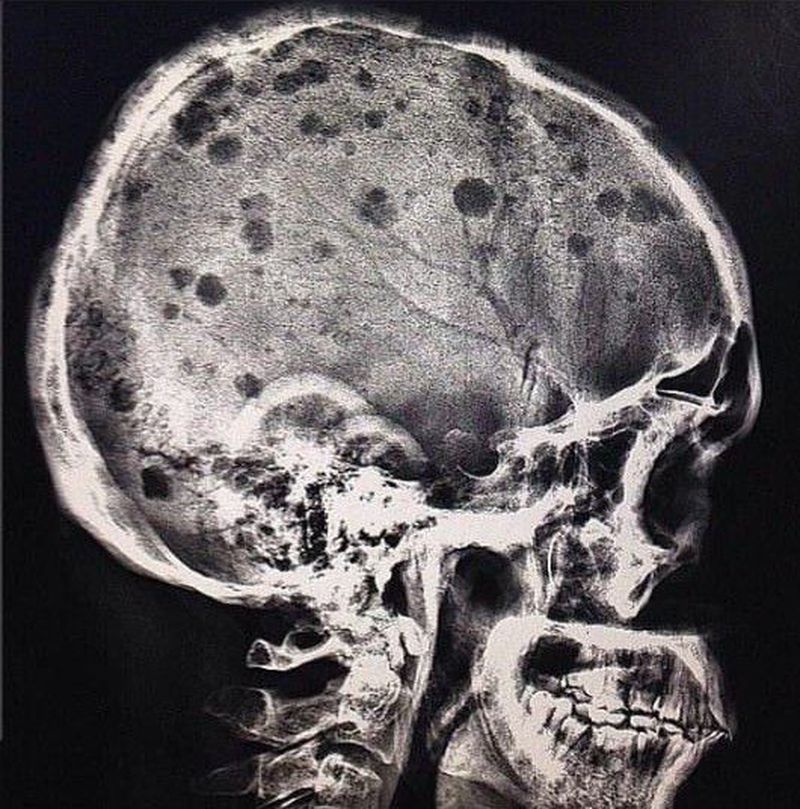

Multiple myeloma

Radiographic image of multiple myeloma is that of multiple,small, well circumscribed,lytic,punched out, round lesions within the skull,spine,pelvis. The lesions tend to vary slightly in size